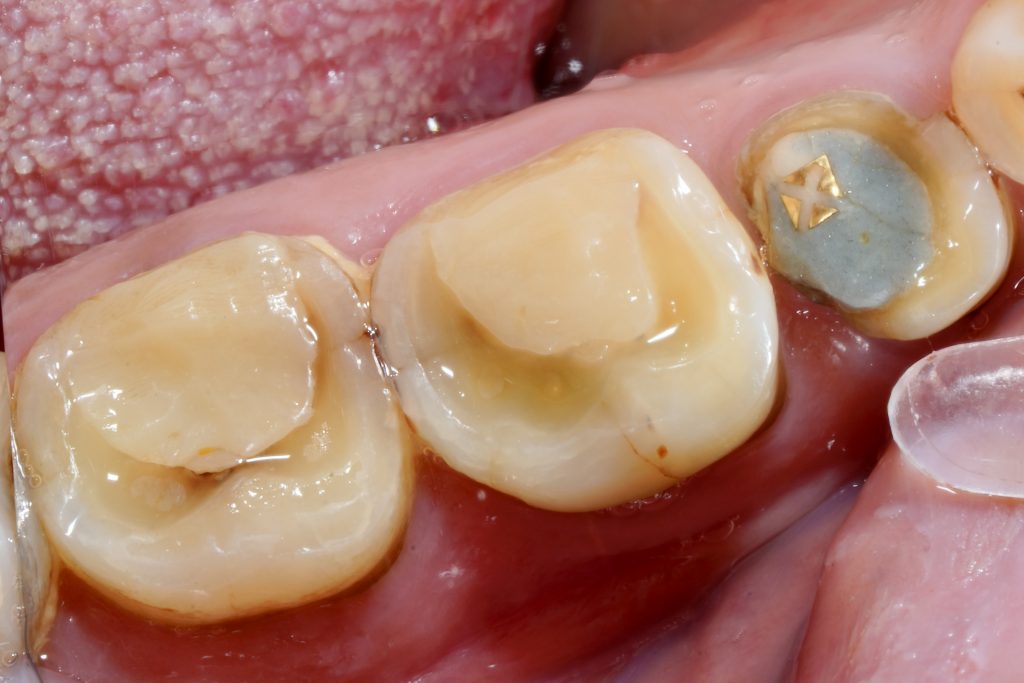

3️⃣ Canal Exploration and Working Length

Under high magnification, all canal entries were negotiated using #08–#10 K-files (Fig 3). Electronic apex locator and radiographs determined working lengths. In #6, an MB2 canal was located and confirmed with micro-ultrasonic troughing.